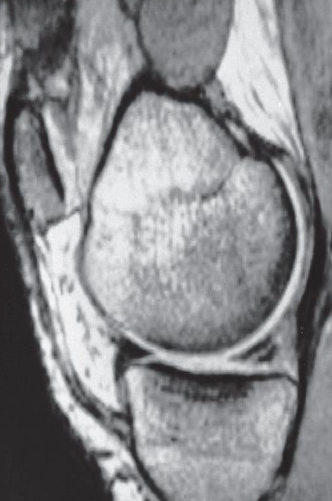

Imaging modality? Sagittal MRI through the medial part of the knee

joint

Finding tear in the posterior horn of the medial meniscus . The anterior horn appears normal.

Diagnosis the medial meniscus Tear